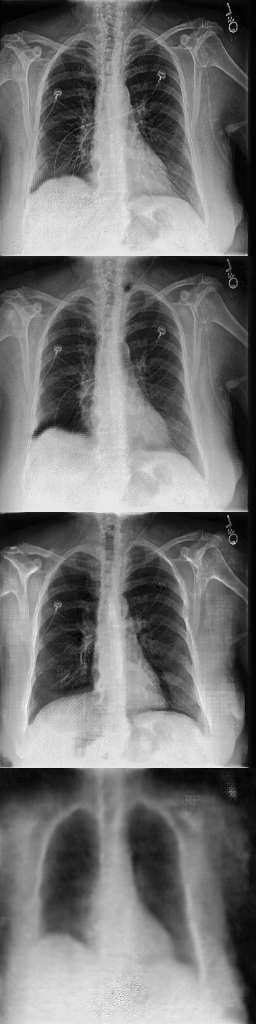

For the Chexpert dataset introduced in [12], we used a training set of 14179 images of healthy subjects and 16776 images of subjects that suffer from pleural effusions. The test and validation set each consist of 200 images for each class.

Refer to captionInput rpsubscript𝑟𝑝r_{p}Refer to captionOutput ahsubscript𝑎a_{h}Refer to captionDifference |d|𝑑|d|Refer to captionInput rpsubscript𝑟𝑝r_{p}Refer to captionOutput ahsubscript𝑎a_{h}Refer to captionDifference |d|𝑑|d|Refer to caption11100DeScarGANFP-GANVAGANVAE

Figure 6: Comparison of our DeScarGAN against FP-GAN, VAGAN and VAE for two samples of the Chexpert dataset.

DeScarGAN achieves better classification results than the pure classification networks Dclssubscript𝐷𝑐𝑙𝑠D_{cls} and Densenet169, indicating that the GAN mechanism supports the classification network. The results of the different methods are visualized in Figure 6. We observe that the VAE fails to detect pleural effusions. Although FP-GAN detects similar regions as our method, the generated maps appear blurry and mark regions outside the thorax. The additive map of VAGAN also outlines parts of the arms and upper chest as abnormal. Our method generates the most detailed difference map, not highlighting any regions outside the pleural space.